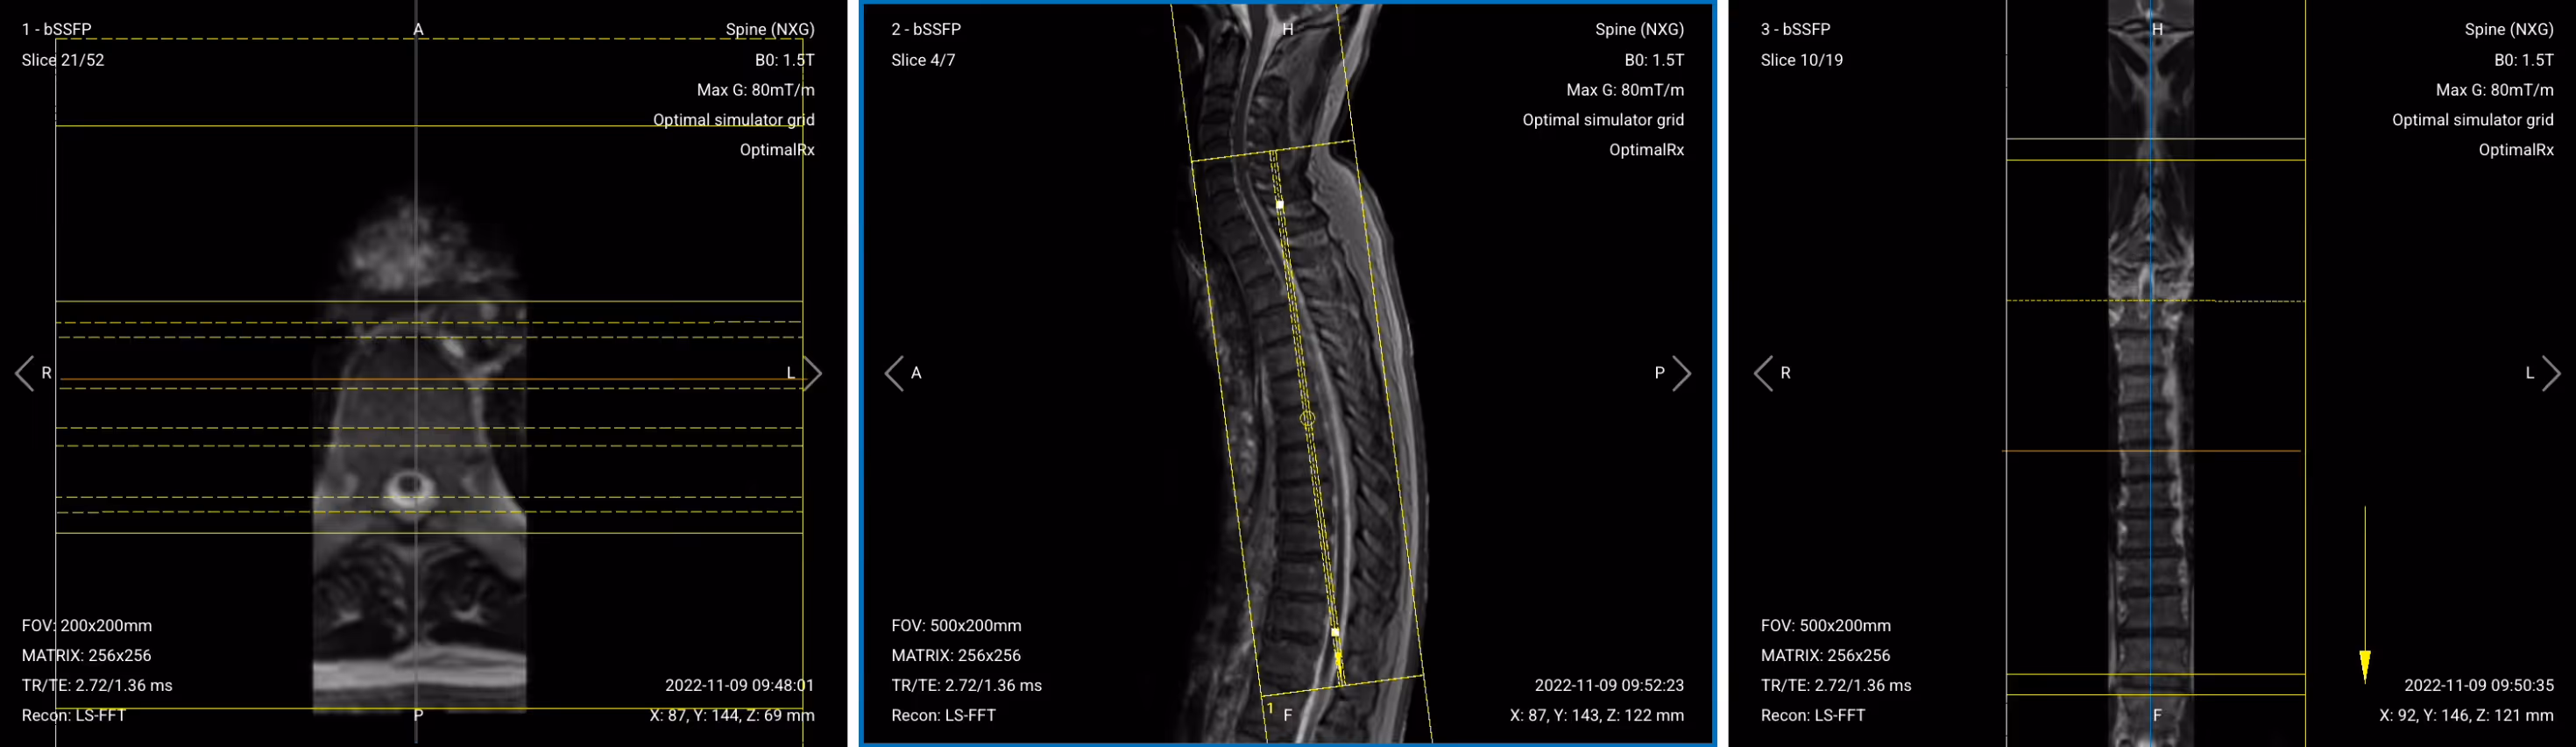

Before we can perform any MRI protocol, we must always capture initial localizer images of the patient. These images act as a guide for planning the detailed scans we will perform next.

We should always capture localizers in three planes:

Once acquired, upload the initial localizer images into the three viewports.

Then, scroll through each of the image stacks to locate a central slice that clearly shows the anatomy of the thoracic spine.

✅ Correct Setup of Localizer Images for Thoracic Spine MRI: